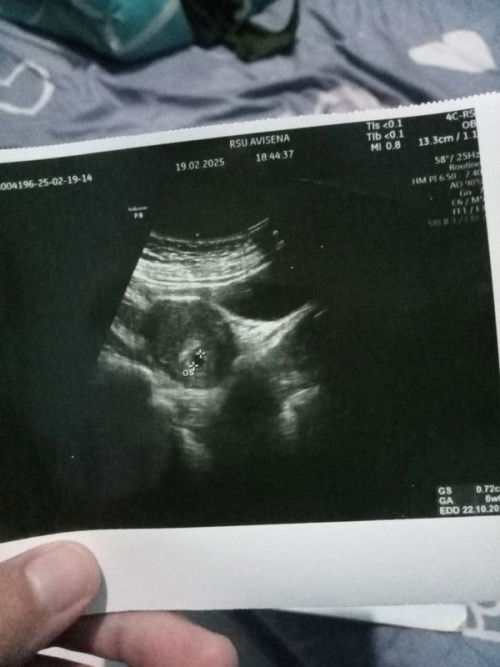

Saya baru lahiran 5bulan lalu secara SC, trs karena sering kram perut makanya penasaran nyoba lah tespek tadi jam 4 subuh hasilnya positif udh 3 kali tespek d jam berbeda hasilnya masih positif Minta doanya ya mudah2an d lancarkan gaada kendala apa2 selama hamil sampai melahirkan d mudahkan rezeki dan d sehatkan adik bayinya aamiin. Bunda2 boleh sharing siapa tau ada yg pengalaman kyk saya biar bisa kasih saya semangat buat jalani nya;))#sharing #Sharingdong_Bund